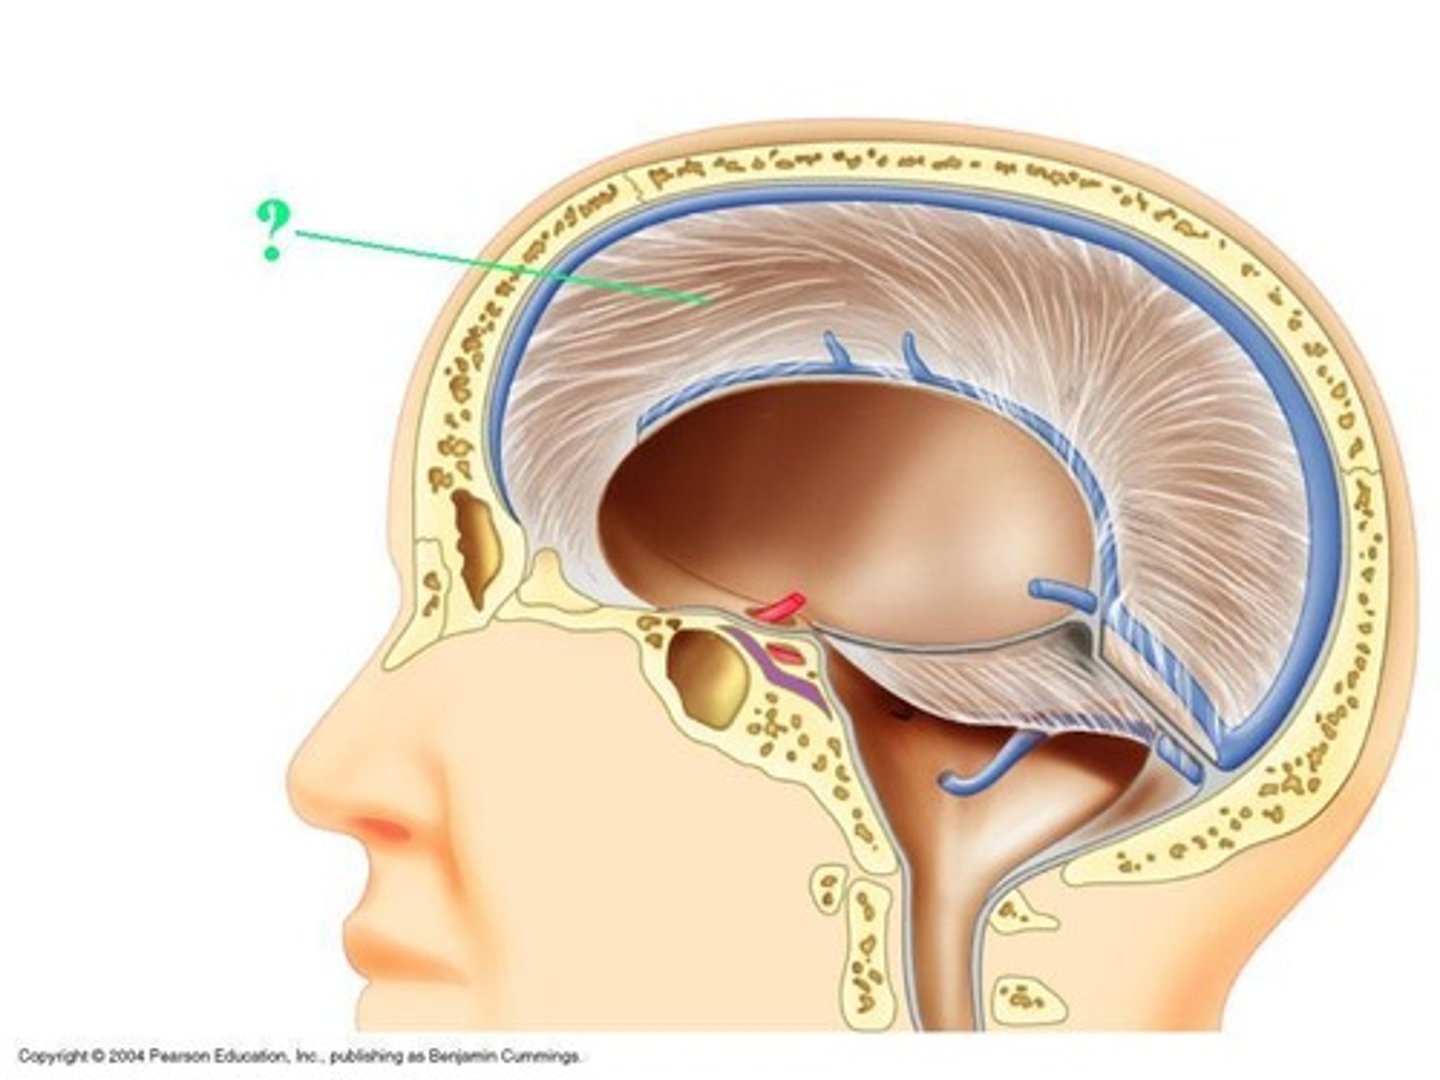

falx celebri

large, sickle-shaped, separates the cerebral hemispheres

tentorium cerebelli

2nd largest, crescent-shaped, separates cerebrum (occipital lobes) from cerebellum (arrow #5)

falx cerebelli

seperates the two hemispheres of the cerebellum. it lies inferior to the tentorium cerebelli, separating cerebellar hemispheres (arrow #7)

diaphragm sellae

smallest infolding covering pituitary gland & sella turcica

superior sagittal sinus